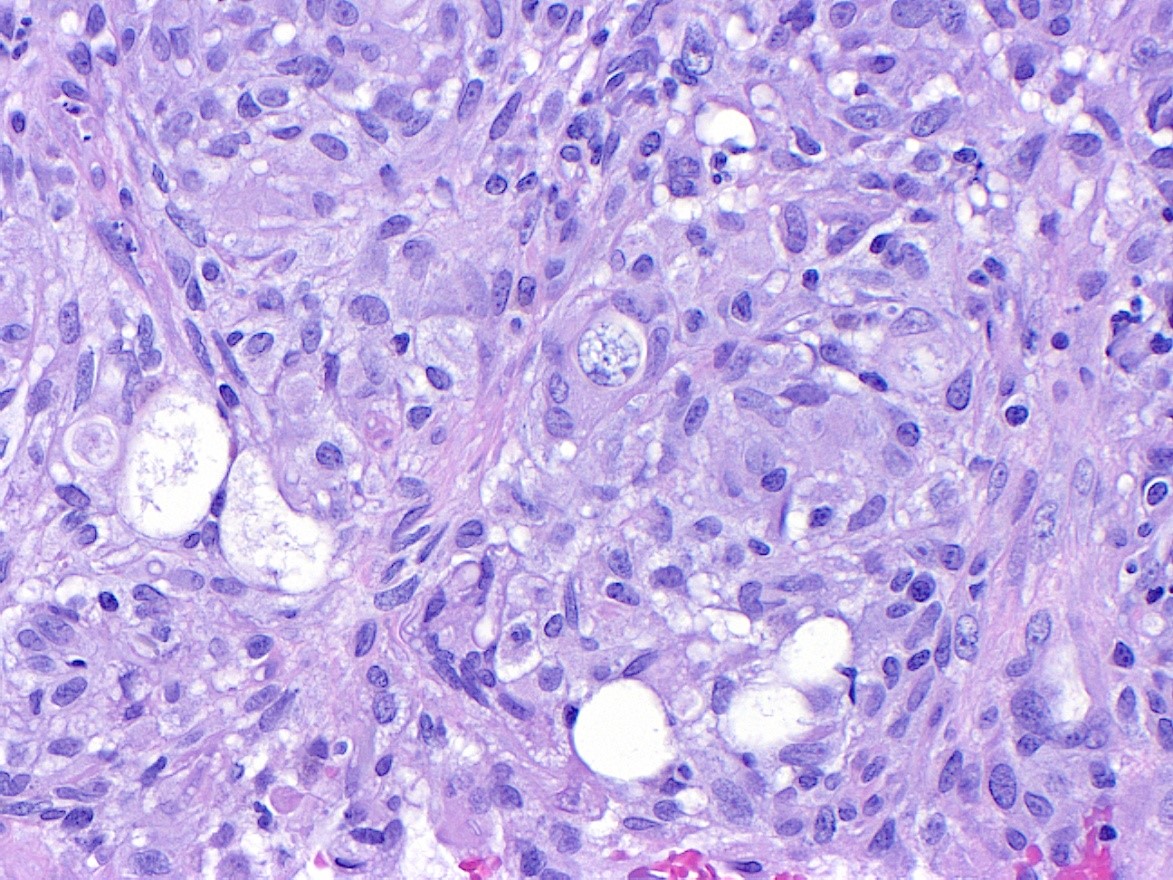

Figure 7. H&E, 20x magnification.